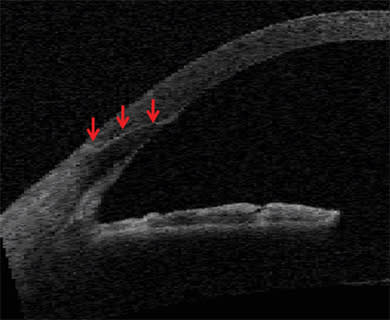

For the capsulorhexis, the OCT detects the iris boundaries so the laser can be safely directed inside the iris even if it is not dilated symmetrically (Figure 3). Research has shown that the capsular edge tensile strength is equal to that of manual techniques (Figure 4). The laser incision formed with cavitation bubbles may have improved strength and resistance to manual trauma during phaco and lens implantation, which could reduce capsular extensions. Symmetrical uniform fibrosis and healing may also be important for accommodating IOLs that rely on symmetrical contractile forces to translate into axial movement.

Figure 4: Electron microscopy of edge of femtosecond laser-cut human anterior lens capsule showing smoothness of the cut (red arrows) comparable to manually created anterior capsulorhexis.